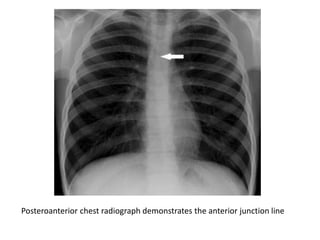

Posteroanterior chest radiograph

demonstrates the anterior junction line

Posteroanterior chest radiograph demonstrates the anterior junction line